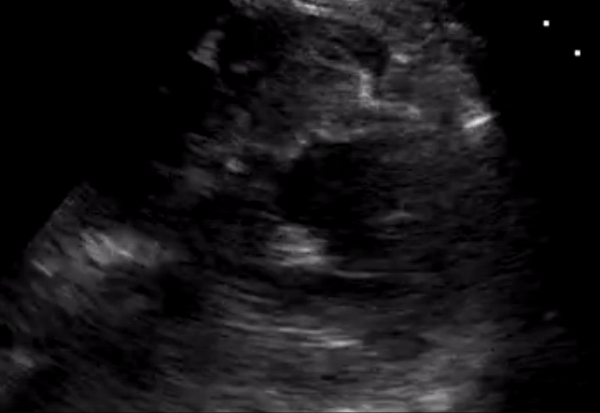

IVC

IVC with small diameter and total collapse during inspiration: In this sagittal view, just to the right of the midline, the right ventricle is seen on the right side of the clip, and the inferior vena cava (IVC) is visible below the liver in its longitudinal view. The IVC has a small diameter, measuring less than 1 cm, and shows complete collapse during inspiration, which is a strong indicator of hypovolemia.